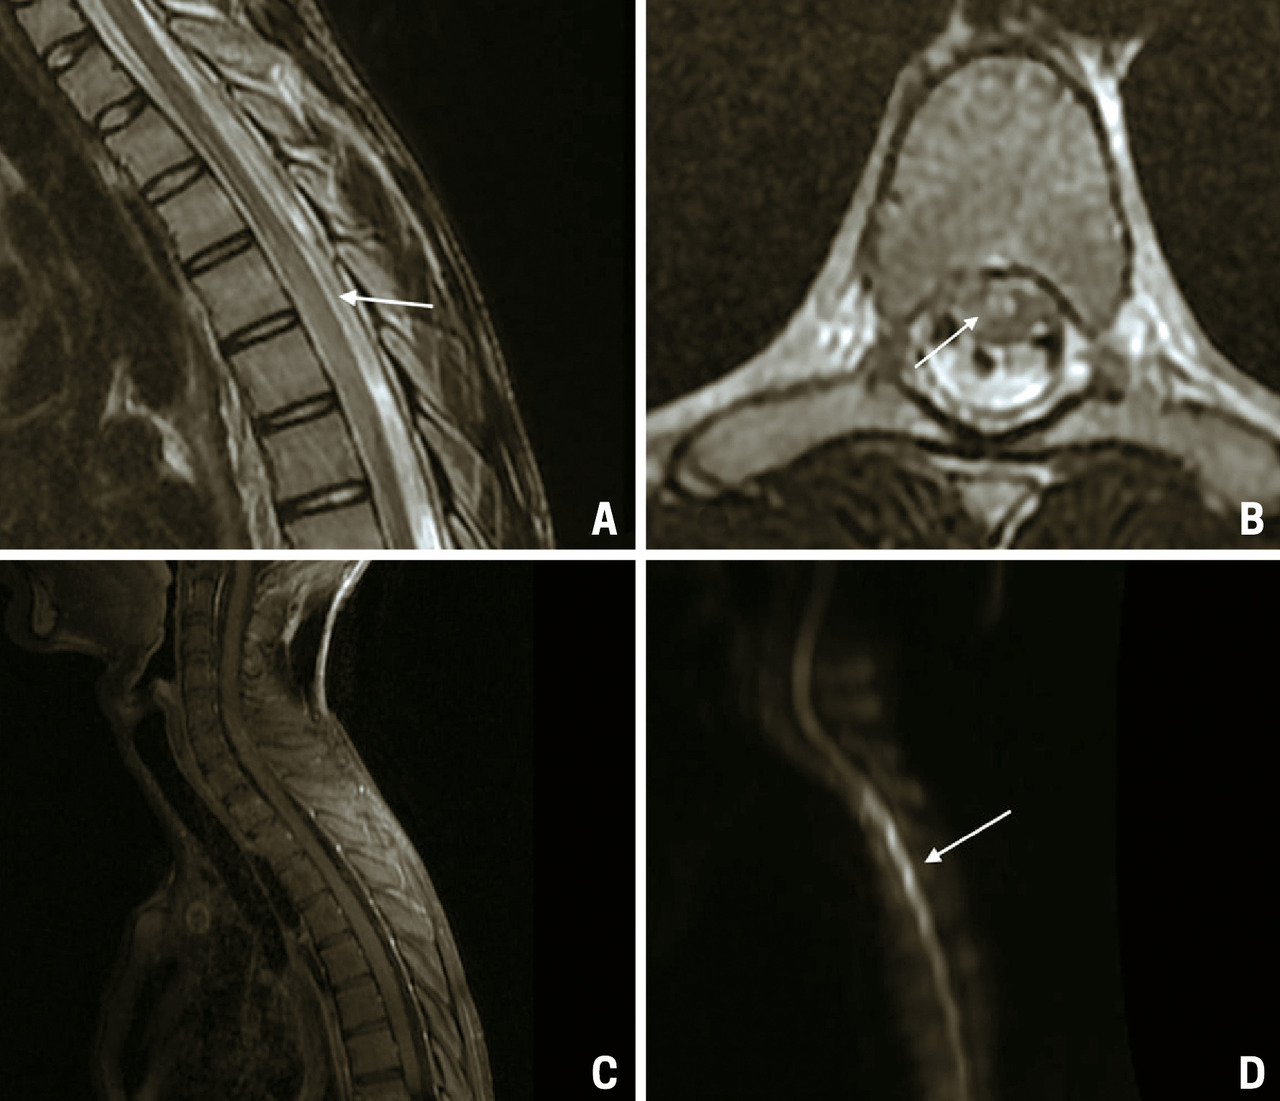

Une IRM médullaire est réalisée en urgence, mettant en évidence une anomalie de signal centromédullaire étendue de T4 à T6 en hypersignal T2 – réalisant un aspect en « œil de hibou » –, avec une restriction en diffusion et sans prise de contraste après injection de gadolinium (fig. 1).

Une IRM de contrôle est réalisée à J20, montrant une évolution de la myélite vers une cavitation avec atrophie médullaire (fig. 2).

L’installation brutale du déficit, l’absence d’anomalies associées et l’aspect radiologique sur les IRM initiale et de contrôle permettent d’évoquer une origine ischémique de cette myélite du territoire spinal antérieur.

Le diagnostic d’ischémie médullaire reste difficile à poser avec une IRM à l’aspect souvent normal de la moelle épinière sur les séquences T1 et T2. Si le tableau clinique évoque la possibilité d’une ischémie, les séquences de diffusion doivent compléter le bilan IRM. Les résultats de l’IRM de diffusion demeurent cependant aléatoires en raison d’une qualité d’image souvent insuffisante. Le contrôle IRM réalisé après vingt-quatre à quarante-huit heures confirme le diagnostic en visualisant un signal hyperintense en T2 de topographie centromédullaire de part et d’autre de la ligne médiane, correspondant au territoire de l’artère spinale antérieure (image en « œil de serpent » ou en « œil de hibou »). Au-delà de quarante-huit heures, l’IRM peut visualiser un effet de masse, et une prise de contraste est souvent observée. À la phase séquellaire, il est classique de noter une atrophie médullaire avec de petites cavitations intramédullaires de part et d’autre de la ligne médiane.1